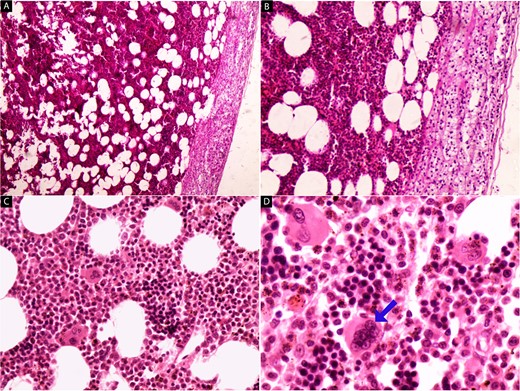

We report the case of a 45-year-old female, who presented to our hospital because of a mass on the right adrenal gland that was discovered incidentally during a periodic echocardiogram without any symptoms on the patient. The patient declared a history of excisional biopsy for a benign breast mass, a medical history of medication-controlled hypertension for 5 years, and Type 2 diabetes for 10 years but the family history was unremarkable. Laboratory investigations, including complete blood count and biochemical markers, were within normal limits. Imaging studies were performed, including contrast-enhanced computed tomography (CT) of the abdomen. The CT scan revealed a large, well-defined, heterogeneous mass measuring 13 × 12 × 9.5 cm, located in the right adrenal gland. The mass contained areas of high attenuation, suggesting recent hemorrhage, along with fat-density areas consistent with adipose tissue (Fig. 1). There were no signs of invasion into adjacent structures or lymphadenopathy. Based on the clinical presentation and radiological findings, the provisional diagnosis was a hemorrhagic giant adrenal myelolipoma. The patient underwent a right open adrenalectomy to address a large mass and minimize potential complications such as hemorrhage. Intraoperatively, a large, encapsulated mass was found in the right adrenal gland. The mass was carefully dissected from surrounding tissues, and the adrenal gland was removed and sent to the pathology department. There were no intraoperative complications. Upon gross examination, a mass with a total weight of 44.5 g was observed, measuring 15 × 10.5 × 5 cm. The mass displayed encapsulation and exhibited a rubbery to cystic consistency, with areas of hemorrhage evident. The cut surface revealed a heterogeneous composition, ranging in color from yellow to black and presenting a gelatinous texture. Multiple sections of the specimen were subsequently submitted for further analysis (Fig. 2). Microscopic examination revealed a mixture of mature adipose tissue and hematopoietic elements, including myeloid and erythroid cells. Focal areas of hemorrhage and hemosiderin deposits were observed within the tumor (Fig. 3), consistent with the radiological findings. Histopathological examination confirmed the diagnosis of a hemorrhagic adrenal myelolipoma. There was no evidence of malignancy. The patient had an uneventful postoperative recovery and was discharged on the 5th day after surgery. Follow-up at 6 months showed no complications, and imaging studies demonstrated no evidence of tumor recurrence. The patient continues to be asymptomatic and is under regular surveillance.

Hematoxylin and eosin-stained images (a–d) of the adrenal tumor. At low magnification (a, b), a mixture of mature adipose tissue with hematopoietic elements is evident, and the preserved adrenal tissue is observed in the upper right part of the tumor (40× and 100×). High-power magnification (c, d) reveals the presence of megakaryocytes (arrow) amidst myeloid and erythroid cells, along with hemosiderin deposits (200× and 400×).